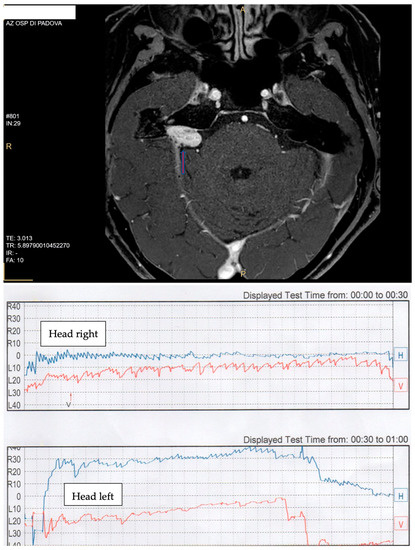

| BP | female | 54 | intrameatal (0.54 cm) | right | apogeotropic direction-changing PPN | first sign | not responsive |